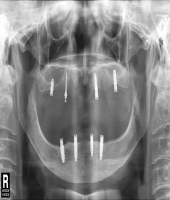

| ● 진료과목 : [임플란트] 하악 전치부 골폭이 좁은 경우

| ● 내용 : 일체형 임플란트로 . . |